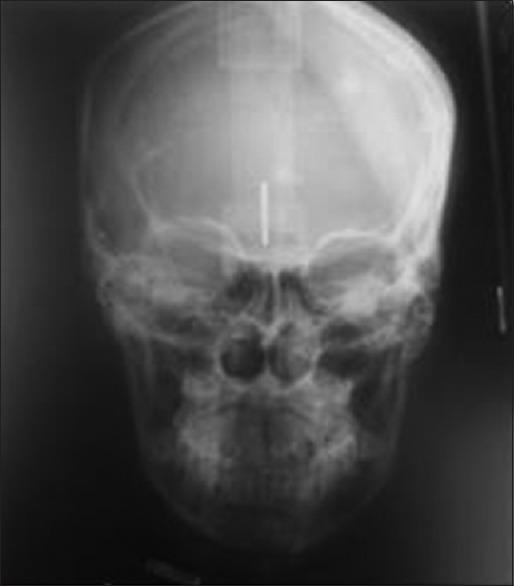

Unilateral condylar hyperplasia is an uncommon condition with unknown etiology which causes overdevelopment of condyle leading to facial asymmetry, mandibular deviation, malocclusion, and articulation dysfunction. Two Indian families with unilateral condylar hyperplasia are presented where the similar abnormality was also detected in one of their parents. The condylar hyperplasia in these two families indicates that mandibular condylar hyperplasia could be genetic in origin.

单侧髁突增生是一种病因不明的罕见病症,它会导致髁突过度发育,进而引起面部不对称、下颌偏斜、错牙合畸形及关节功能障碍。本文报告了两个患有单侧髁突增生的印度家族,在他们的一位家长中也检测到了类似异常。这两个家族中的髁突增生表明下颌髁突增生可能起源于遗传。